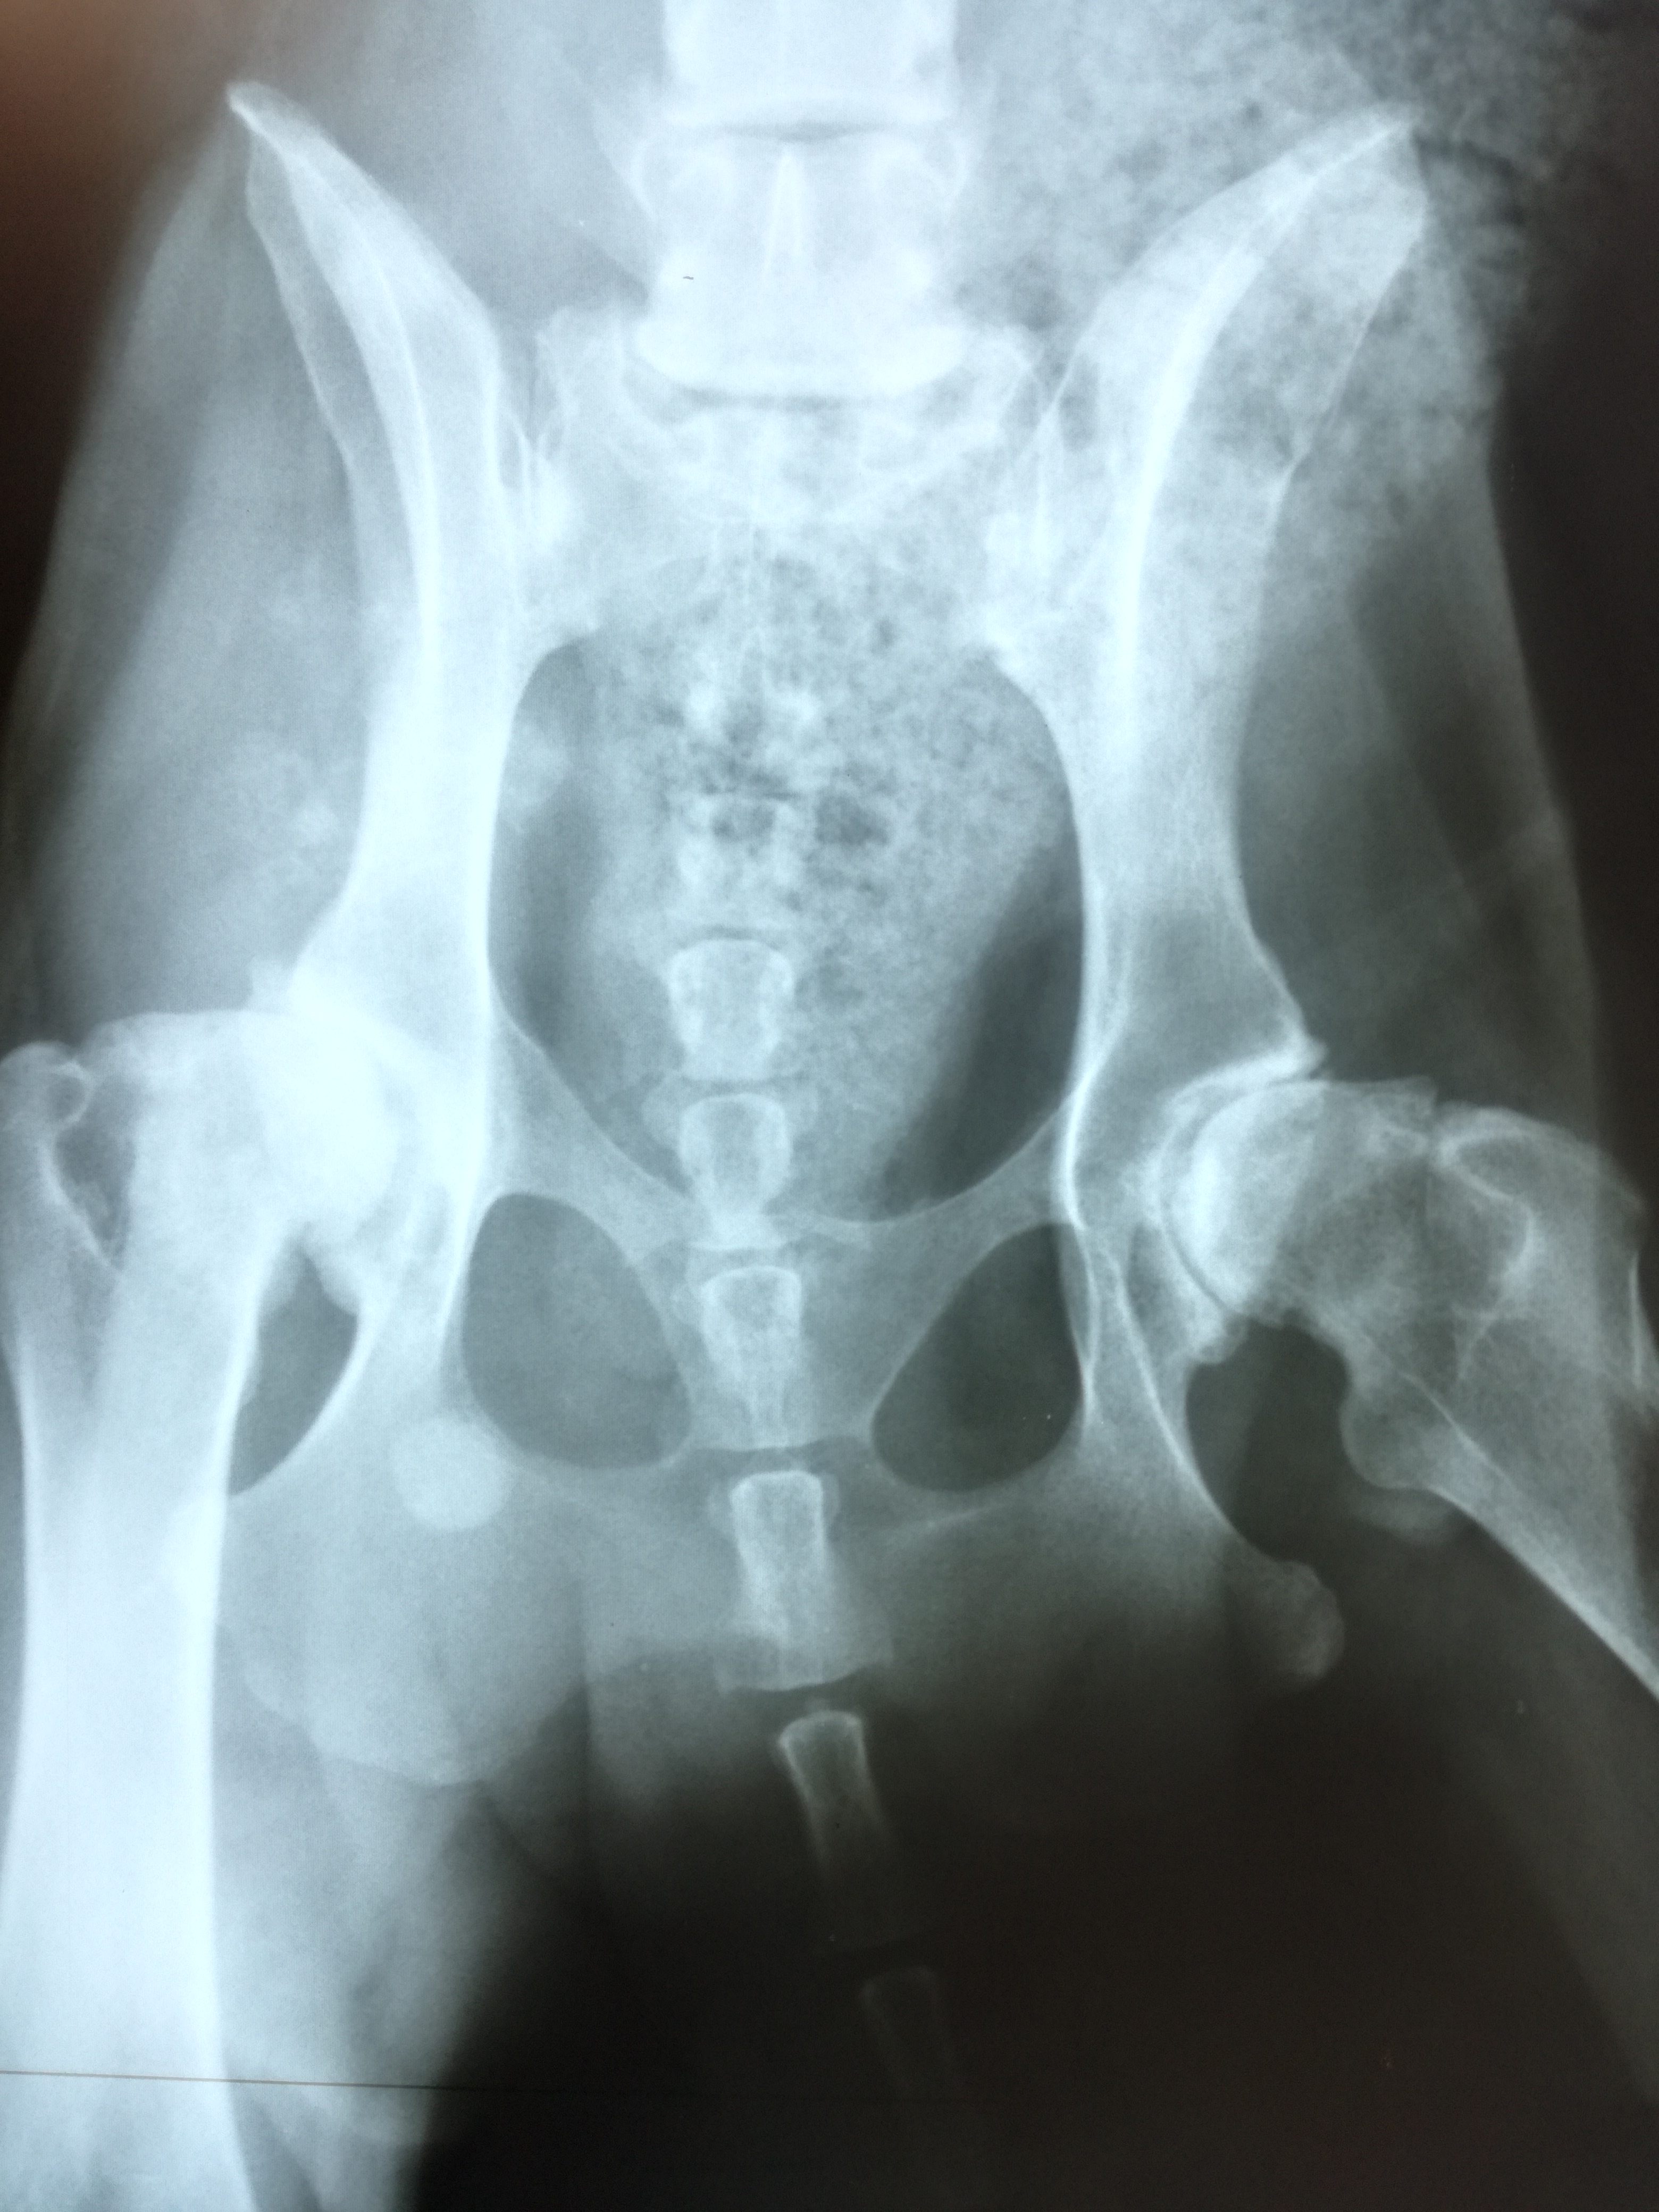

Stérilisation Hortense+chaîne mammaire+radios+PS+++

Alors? alors l’ovariectomie d’Hortense ainsi que l’ablation d’une chaîne mammaire n’ont pas été du luxe!!! illustration en image:

Cancéreux? un prélèvement a été envoyé pour analyse. Mais selon les vetos, c’est toujours cancéreux, reste à connaître le stade pour se prononcer sur la gravité. Parfois l’ablation des organes touchés suffit à guérir le chien.

Nous avons profité de l’anesthésie pour faire une radio des poumons, il n’y a pas de métastases, c’es LA bonne nouvelle. Il n’y en aura pas tant que ça concernant la santé d’Hortense….

Quid de sa boiterie?

Au vu des radios il s’avère que toute opération du genou est impossible, il n’y a pas de prothèse du genou chez le chien. Peut être amputer pour supprimer la douleur, de toute façon Hortense ne prend aucun appui sur sa pauvre patte quasiment inerte, ni dans le mouvement, ni en statique….à voir….l’amputation n’est pas une décision facile à prendre.